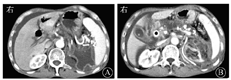

血常规WBC计数为2.74×109/L,RBC计数为3.12×1012/L,PLT计数为84×109/L。血清淀粉酶为112 U/L,胆红素水平正常。肿瘤标志物:AFP正常,CEA为11.07 μg/L,CA19-9为205.50 kU/L,CA125为116.90 kU/L。HBsAg为172.62 mIU/mL,其他乙型肝炎标志物均正常。2016年6月24日,上腹部CT平扫和增强(图1)示:①胆系扩张,胆总管下段有软组织密度影并强化,需考虑占位可能;②胆总管下段多发结石;③慢性胰腺炎并胰管明显扩张;④胆囊结石并胆囊炎;⑤肝硬化;⑥左肾结石,左肾巨大囊肿。MRI和MRCP检查(图2)示:①胆总管下段结石并胆系扩张;②胆总管下段狭窄,需排除占位;③左肾区巨大囊肿。7月2日行内镜下逆行胰胆管造影术(endoscopic retrograde cholangiopancreatography,ERCP),内镜显示食管静脉曲张(重度),胆管造影示胆总管中段明显狭窄,狭窄处长约2.0 cm,狭窄以上肝外胆管扩张,术中胆管腔内超声(intraductal ultrasonography,IDUS)检查狭窄处胆管未见明显异常,造影未见明确结石影,沿胆总管导丝置入覆膜金属支架于狭窄处。7月7日泌尿系统多普勒超声检查示左肾窝异常回声团块,考虑左肾囊肿可能。7月9日计算机断层扫描泌尿系统延时成像(computed tomographic urography,CTU)(图3)示:左肾区囊性病灶未见造影剂进入,提示假性囊肿形成可能性大。7月20日肝脏静脉血管造影(computed tomographic venography,CTV)(图4)示:肠系膜上静脉血栓形成,门静脉主干起始处闭塞,门静脉海绵样变性。8月1日复查CT增强(图5)示:①肝内胆管扩张、胆总管内置管术后改变。②慢性胰腺炎;胰尾囊肿引流术后,囊腔内积气。